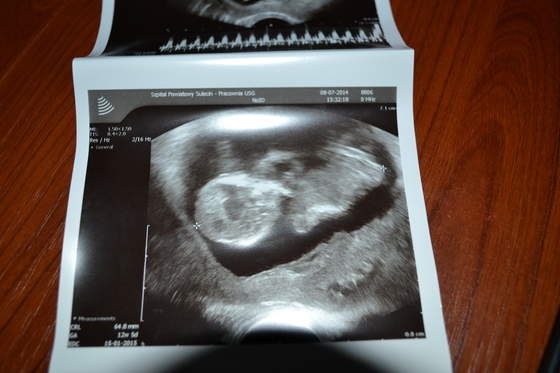

A tu nasz robak

i jego długie nogi, dlatego twierdzę, że to laska z taaakimi nogami

A i dzisiaj na usg wiek dziecka wyszedł idealnie jak wiek według OM, więc oba terminy porodu mi się pokryły. :)